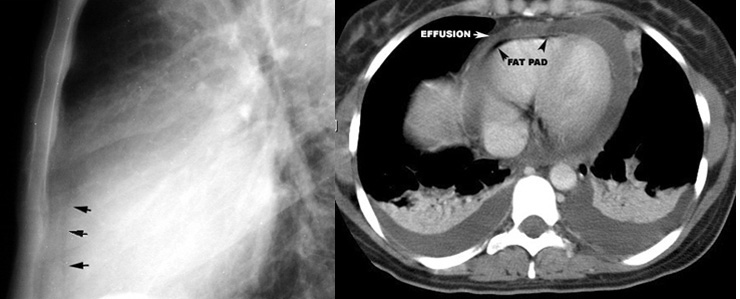

CT : is valuable for detecting loculated pericardial effusions and in detecting pericardial thickening

Epicardial fat pad is displaced posteriorly by pericardial effusion. Low density fluid density around heart.